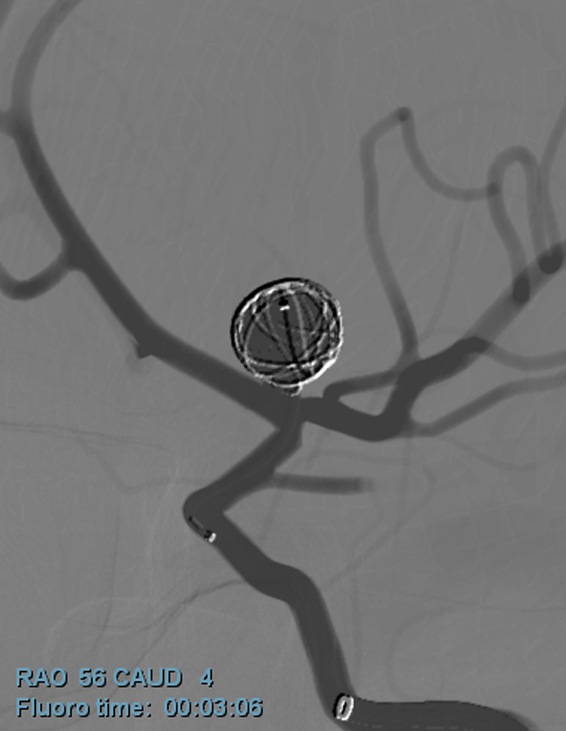

在近五年之內,本院已經處理150例之顱內血管病變切除或夾除手術,170例之顱內血管病變栓塞治療,160例之顱內血管病變加馬刀治療,6例之顱內外動脈吻合手術,2例之頸動脈內膜刮除手術。

各式腦部血管、頸部動脈之病變,包括顱內動脈瘤、顱內動靜脈畸形、腦部毛毛樣血管病變、頸動脈狹窄等。

針對顱內動脈瘤之手術與栓塞治療;顱內動靜脈畸形之加馬刀放射手術、開顱手術、栓塞治療;腦部毛毛樣血管病變之顱內外血管吻合手術;頸動脈狹窄之支架放置、內膜刮除手術等皆在本院能夠得到適當之治療。